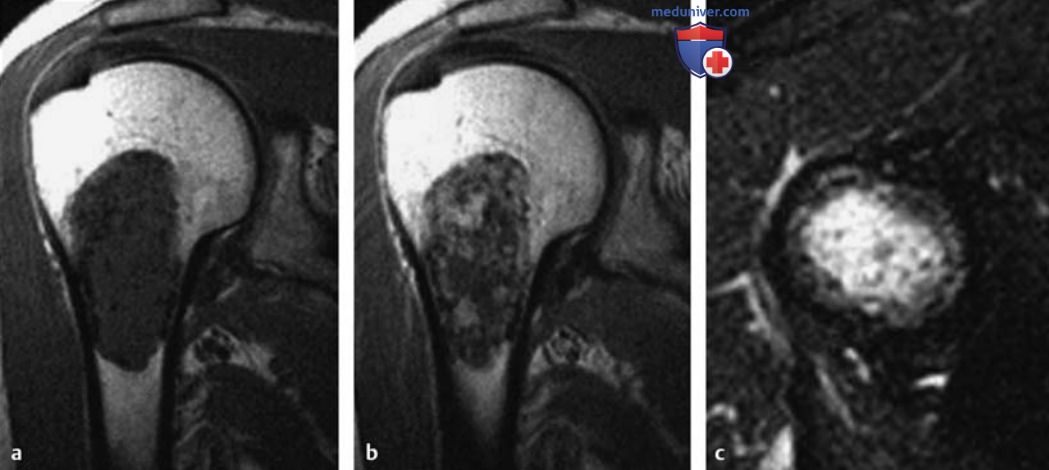

a-c Энхондрома проксимального отдела плечевой кости. Отмечается центральное поражение метафиза с дольчатым строением, которое изоинтенсивно мышцам на Т1в-изображениях и гиперинтенсивно на Т2в-изображениях. Точечная потеря сигнала в гиалиновом матриксе отображает очаги кальцификации. На фронтальном изображении после введения Gd видно усиление сигнала по типу колец и дуг, характерное для хорошо дифференцированных хрящевых опухолей.

а Т1в-SE-изображение во фронтальной плоскости.

b Т1в-SE-изображение после контрастирования.

c Т2в-SE-изображение в аксиальной плоскости.